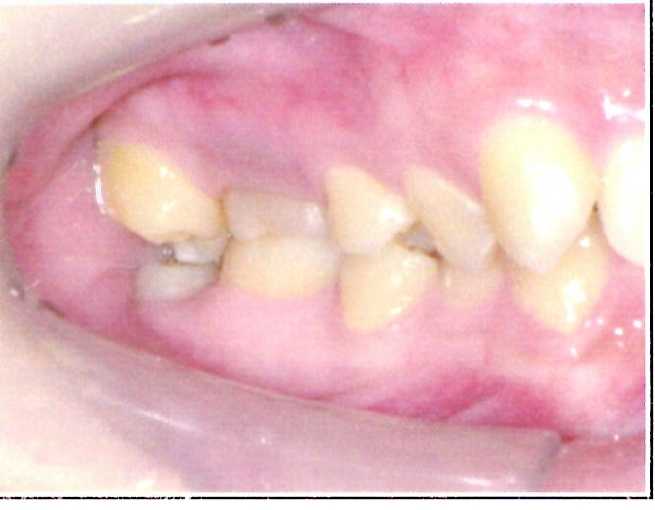

| 主訴・治療前の状態 | 前歯が噛み合っていない状態(開咬傾向)で、犬歯がやや前方に突出しており、見た目にお悩みがありました。 |

| 治療内容 | 上下左右の第一小臼歯(4番)計4本を抜歯し、そのスペースを利用して歯列を整え、前歯の噛み合わせを改善しました。 |

| 治療結果 | 前歯がしっかり噛み合うようになり、見た目も美しく整いました。患者様の満足度が非常に高かった症例です。 |